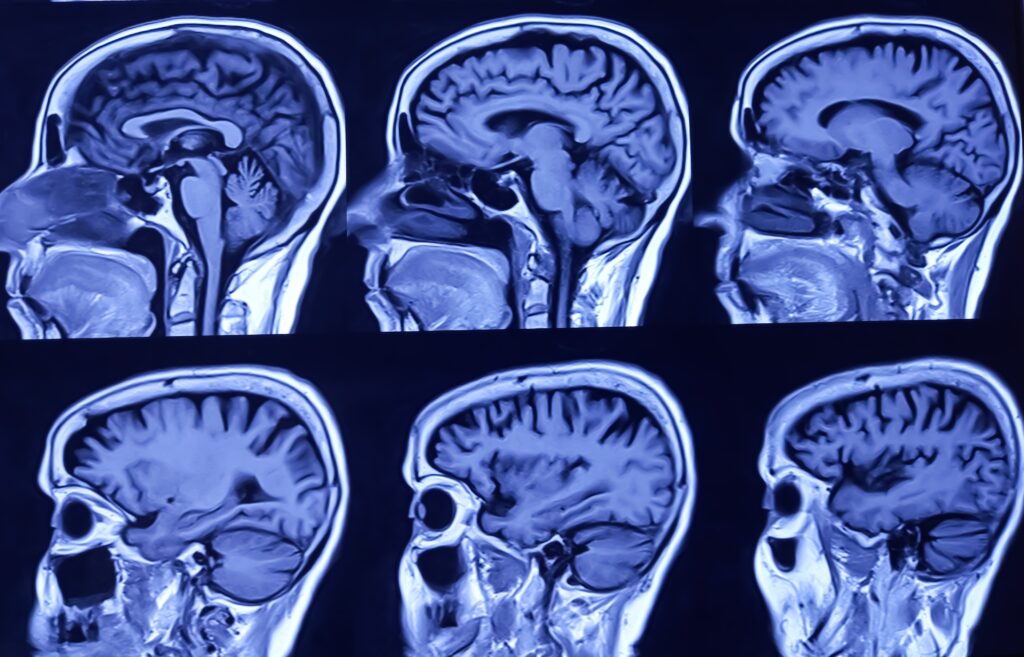

Scientists have identified five major phases of human brain development, with key “turning points” occurring at roughly ages 9, 32, 66 and 83, according to a large study of nearly 4,000 brain scans from infancy to old age.

The research shows the brain does not develop in a smooth, steady way, but instead shifts through distinct eras:

- Birth to ~9 years: Childhood phase, where the brain trims excess connections and rapidly grows in structure.

- ~9 to 32 years: Adolescent phase, marked by improving efficiency of brain networks and cognitive performance.

- ~32 to 66 years: Adult phase, when brain architecture stabilises and becomes more compartmentalised.

- ~66 to 83 years: Early ageing phase, with declining connectivity.

- 83+ years: Late ageing phase, with further network decline.

The strongest shift happens around age 32, when the brain moves into its long-lasting adult mode.

Researchers say understanding these turning points could help explain when the brain is most vulnerable to mental health disorders and age-related cognitive decline.